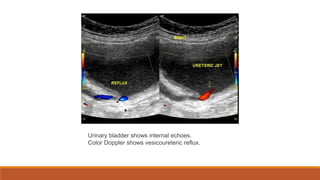

Reflux nephropathy

• Most cases secondary to vesicoureteral reflux (VUR)

Urinary bladder shows internal echoes.

Color Doppler shows vesicoureteric reflux.